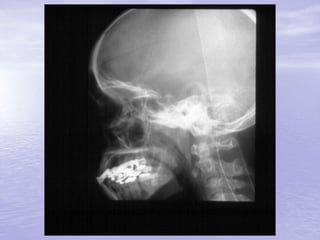

Ferimentos Penetrantes

• Penetração de corpo estranho

intracraniano

• Não deve ser removido no local

• Transporte com corpo estranho fixo

para que o mesmo não produza lesões

secundárias